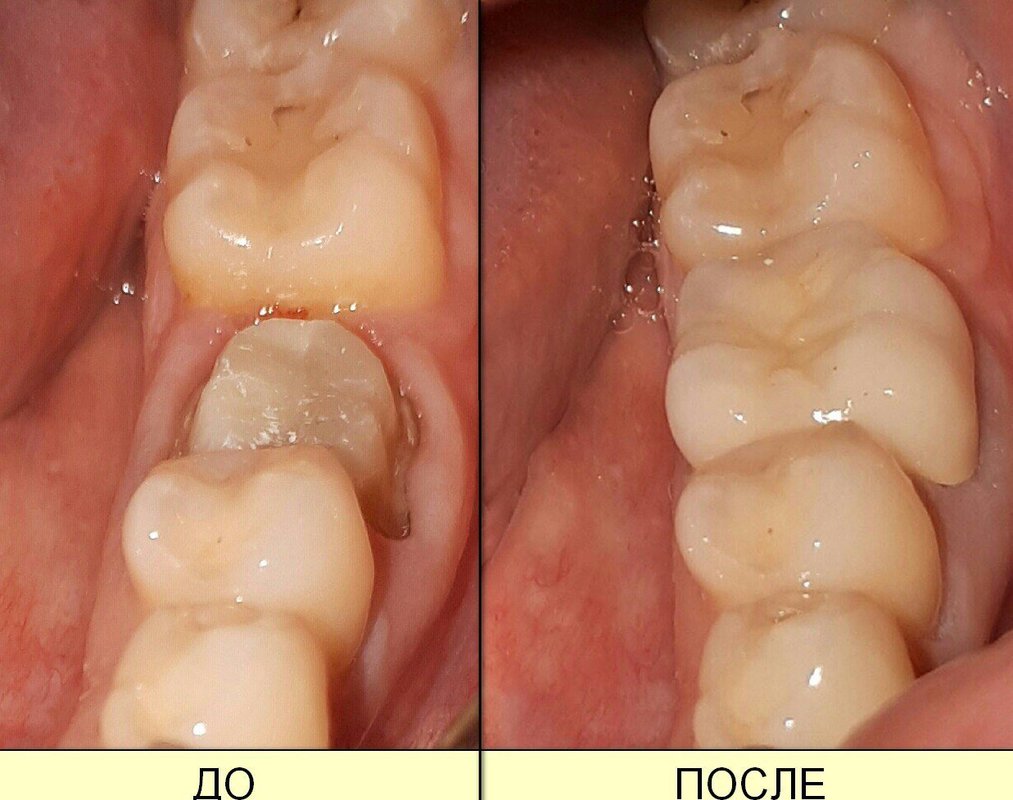

Если вы собираетесь добиться сияющей улыбки, то работу над ней лучше доверить экспертам. В стоматологии Смайл имеется специализированное оборудование для того, чтобы ваши зубы всегда были здоровыми. В нашей стоматологии оказывают услуги лечения кариеса, удаления зубов, отбеливания, исправления прикуса, рентгенологической диагностики, а также установки металлокерамики, брекетов, имплантов, виниров. С нашими специалистами ваша улыбка будет яркой, а зубы крепкими!

Фотогалерея